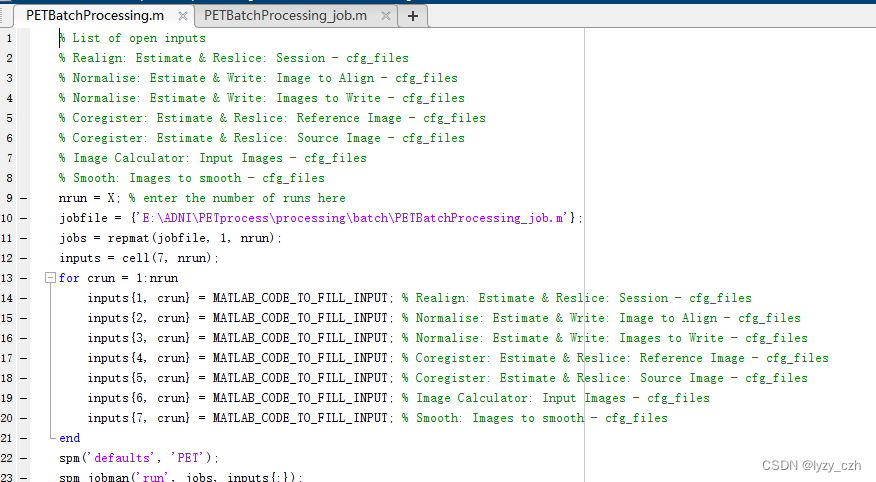

点击保存后,会生成两个.m文件并且自动在matlab打开脚本文件如下:

这里生成的只是模板文件,图像的输入输出还有一些细节是需要我们手动修改实现的。

5、修改脚本代码

1、xxx.m文件代码如下(xxx是你自己的命名)

% List of open inputs

% Realign: Estimate & Reslice: Session - cfg_files

% Normalise: Estimate & Write: Image to Align - cfg_files

% Normalise: Estimate & Write: Images to Write - cfg_files

% Coregister: Estimate & Reslice: Reference Image - cfg_files

% Coregister: Estimate & Reslice: Source Image - cfg_files

% Image Calculator: Input Images - cfg_files

% Smooth: Images to smooth - cfg_files